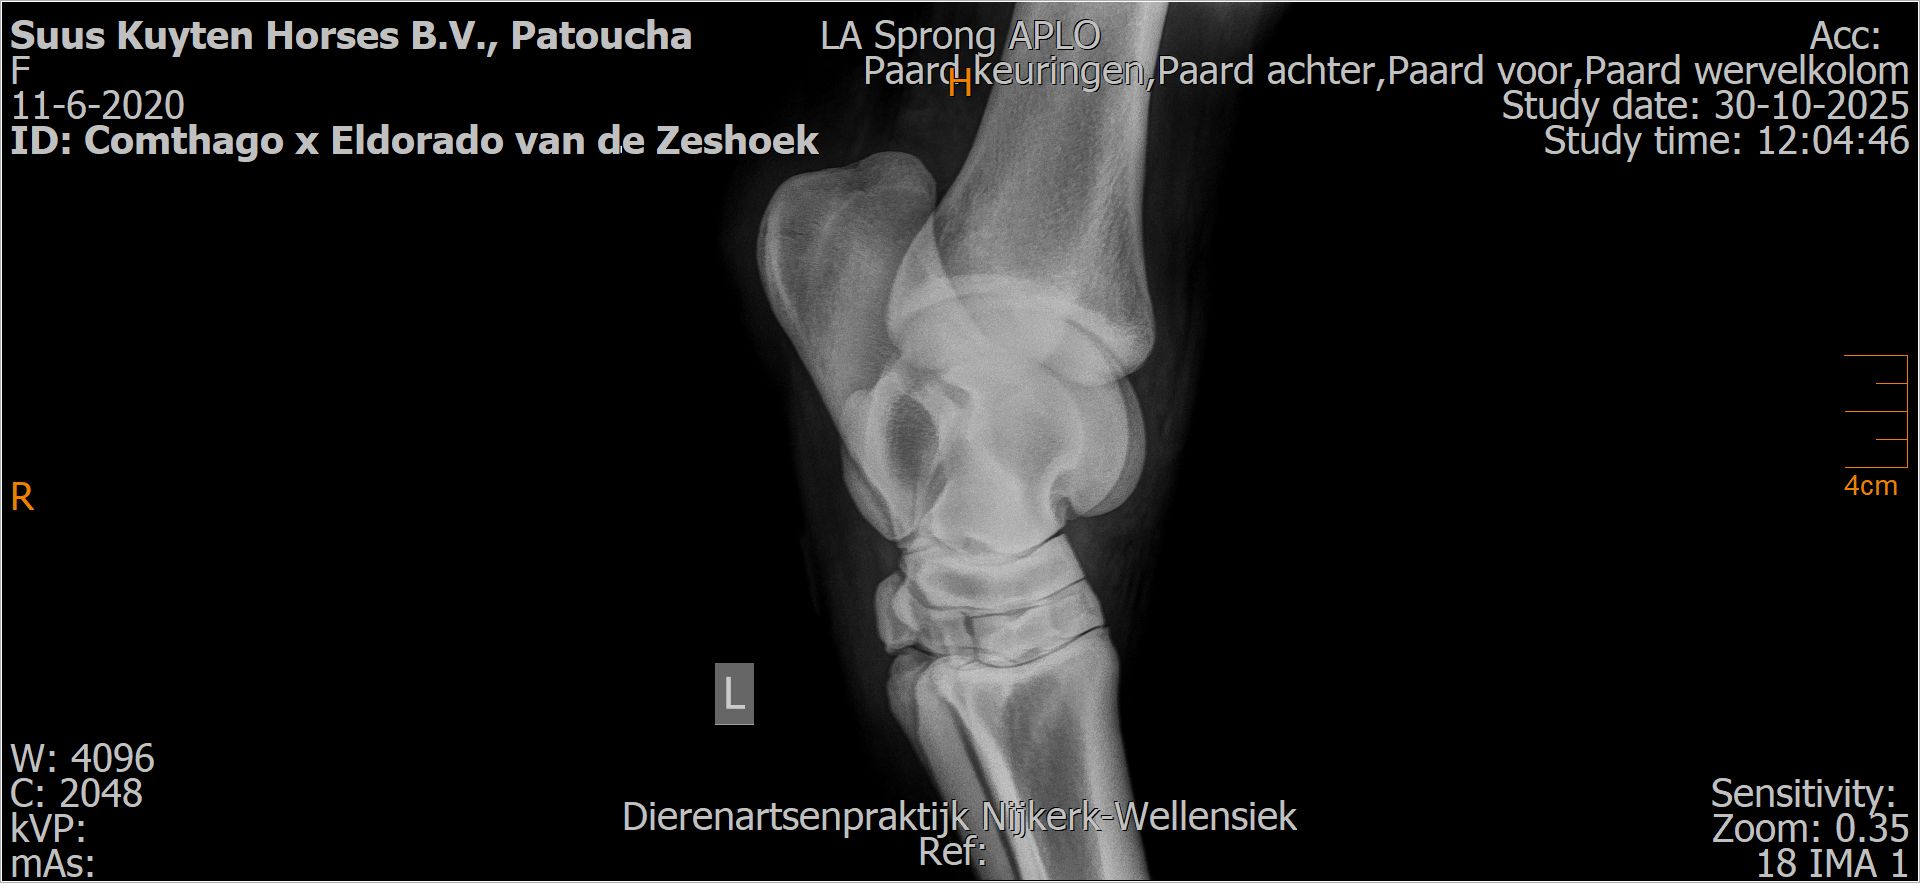

Patoucha

Leeftijd:

7

Röntgenfoto’s